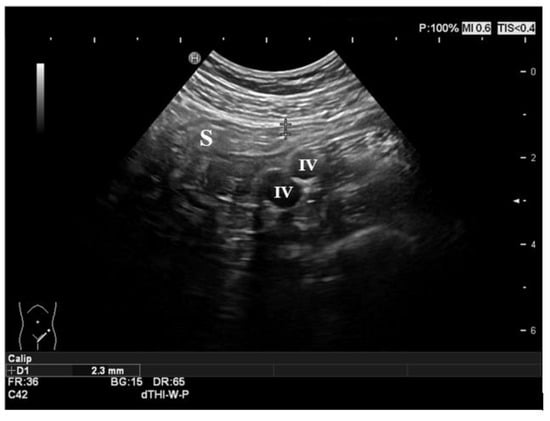

3.1. Ultrasound Features of CD